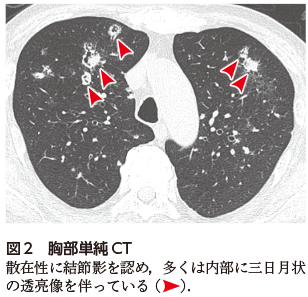

本症例は,成人Still病に対して高用量ステロイドが長期投与され,易感染性宿主となった患者に発症した侵襲性肺アスペルギルス症(invasive pulmonary aspergillosis:IPA)の一例である.胸部単純X線写真では両側肺野に多発する結節影を認め,一部は空洞形成を伴っていた(図1).

結節影の空洞形成は鑑別診断上の重要な手がかりとなることから,胸部画像評価では意識的に読影することが求められる.空洞を伴う多発結節影を呈する疾患としては,IPAや肺ムコール症などの深在性真菌症のほか,敗血症性肺塞栓,肺梗塞,悪性腫瘍の肺転移,多発血管炎性肉芽腫症(granulomatosis with polyangiitis:GPA)などが重要な鑑別にあげられる.特に本症例のような易感染性宿主では,感染症を念頭に置いた評価が必要である.一方で,悪性リンパ腫やCastleman病等のリンパ増殖性疾患も同様に多発結節影を呈することがあるが,空洞形成を伴うことは稀である.

図1